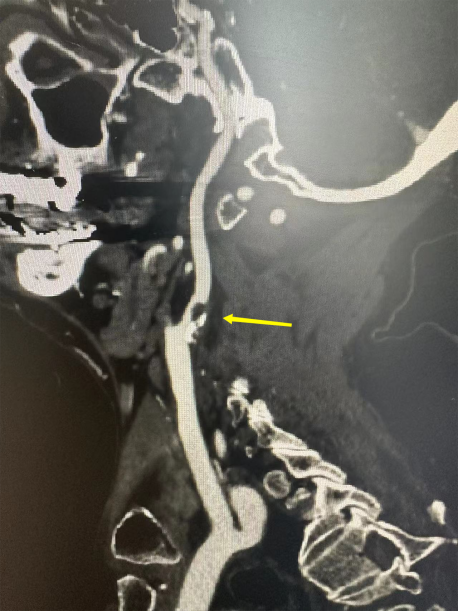

原來,是頸動脈狹窄導(dǎo)致通往他腦部的血流受阻,從而引起腦供血不足出現(xiàn)肢體無力。頸動脈超聲檢查發(fā)現(xiàn),潘大爺?shù)挠覀?cè)頸動脈狹窄已超過了70%,屬于重度狹窄,如果不積極治療,發(fā)生腦梗塞的幾率非常大!

術(shù)前CTA檢查

于是,潘大爺辦理住院。經(jīng)過專家評估并綜合多方面因素后,神經(jīng)外科團(tuán)隊(duì)決定為其行頸內(nèi)動脈內(nèi)膜剝脫術(shù)治療。